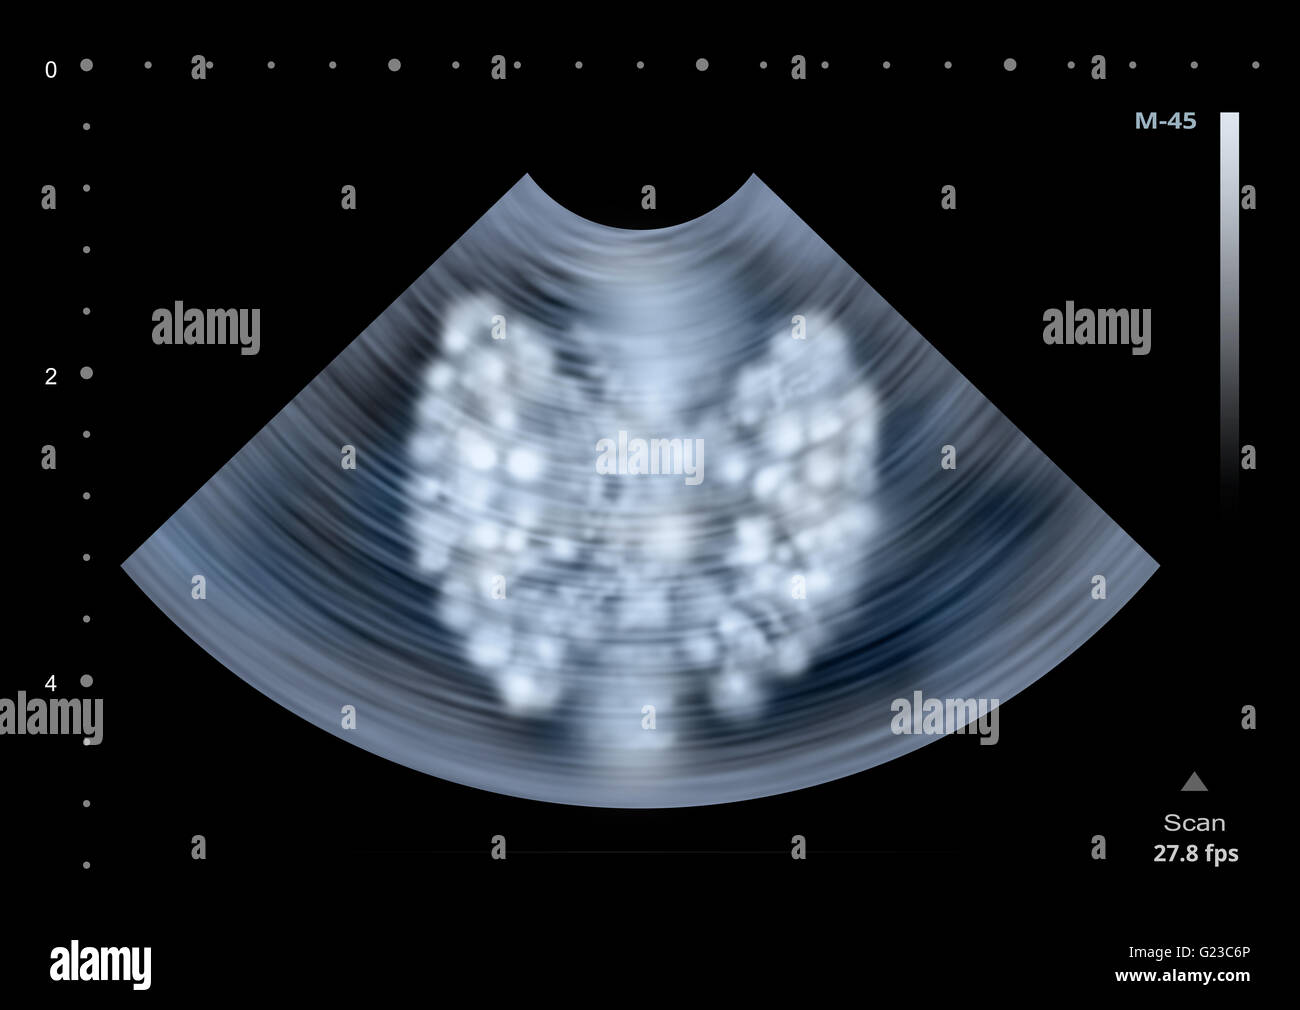

From www.sciencephoto.com

Normal thyroid gland, ultrasound Stock Image C023/9868 Science Thyroid Gland Ultrasound Find out the limitations of this imaging technique and the common questions people ask about it. It does not use ionizing radiation and is commonly used to evaluate lumps or nodules found during a routine physical or other imaging exam. Thyroid ultrasound uses sound waves to produce pictures of the thyroid gland within the neck. Find out the sonographic criteria. Thyroid Gland Ultrasound.